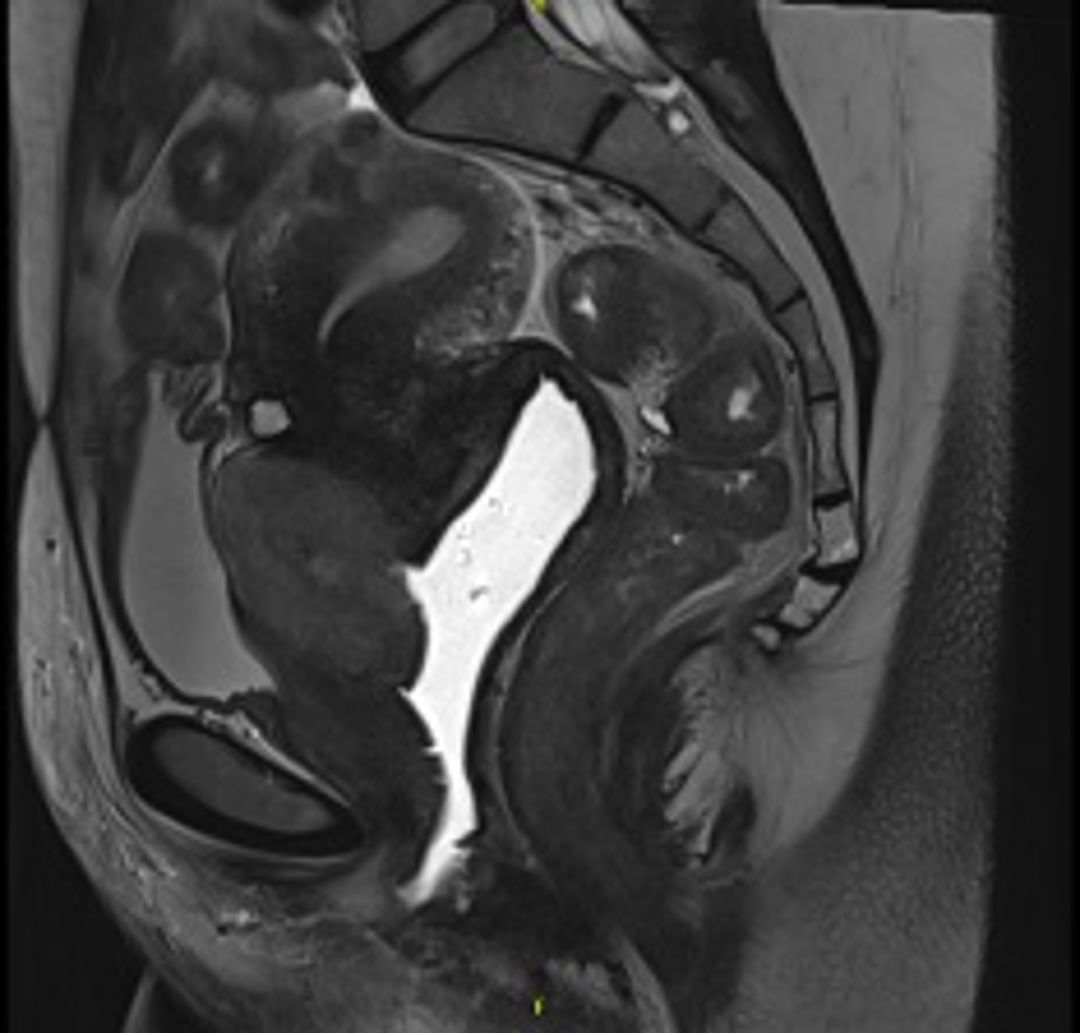

The MRI shows a tumor on the anterior lip of the exocervix showing an exophytic growth towards the vagina, infiltrating mainly the anterior wall and the lateral walls of the upper and middle third of the vagina. It measures approximately 6.2 x 3.6 x 5.5 centimeters(cm) in diameter. Multiple subcentimetric pelvic adenopathies. Image 1.

Figure 1